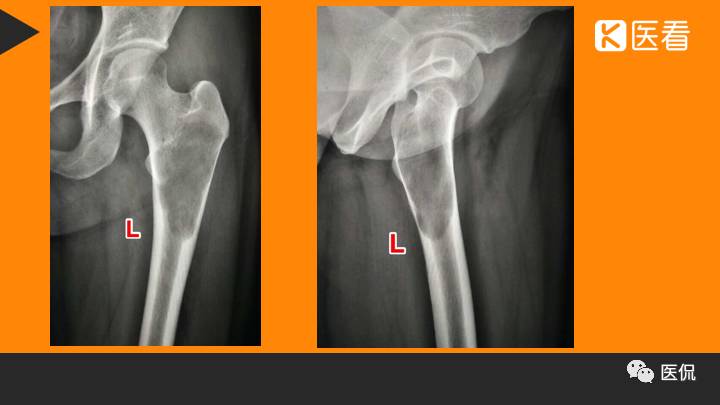

影像资料:

(1)X线 ABC典型的表现为偏心囊状膨胀的溶骨性改变,呈单发或多房的结构,病变与正常骨的分界清楚,边缘光整,有或无硬化、皮质受压、变薄,也可吸收或破裂,突入软组织,形成局限性肿块。位于骨皮质的ABC常呈“吹出”样偏心囊胀,其外常有骨膜新骨形成的薄膜骨嵴,脊柱的ABC也表现为溶骨性膨胀性改变,病变常起始于附件向椎体发展,因此病变常偏于椎体的一侧。病变可跨过椎间关节累及到附近的椎体或肋骨。